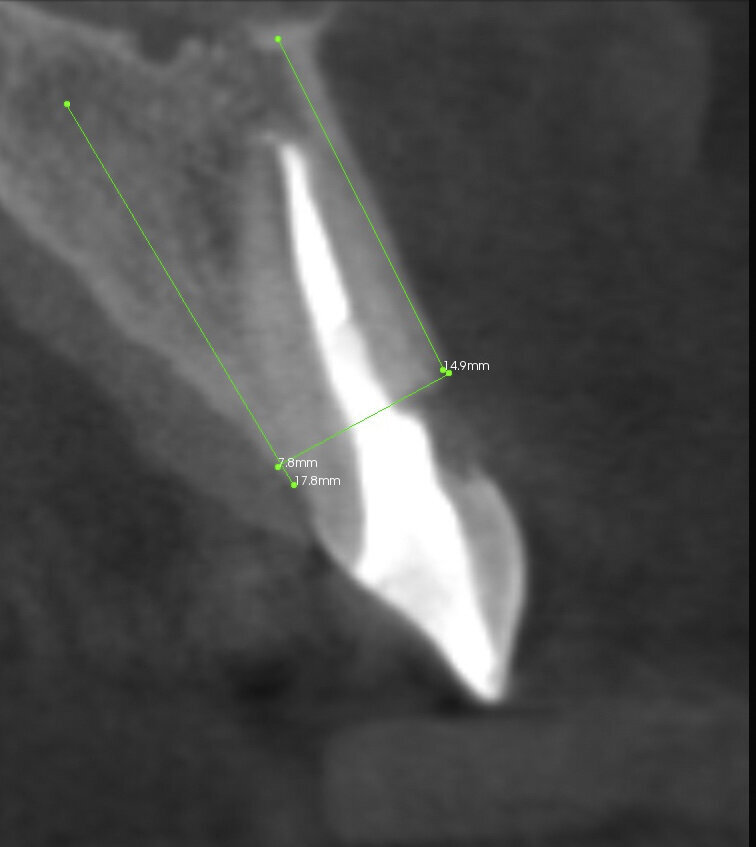

The aim of this article is to present a case of single-tooth prosthetic restoration in the aesthetic zone step by step. The patient was referred to our clinic with a fractured root of tooth #11 (Fig. 1). The cone beam computed tomography (CBCT) analysis confirmed the fracture and revealed external resorption of the root from the vestibular side (Fig. 2). The tooth had to be extracted, and it was decided to follow immediate implant placement with a temporary aesthetic implant restoration. The immediate implant placement was planned with short-term non-occlusal loading.

With the use of the CEREC Omnicam scanner (Dentsply Sirona), scans were taken of both the maxillary and the mandibular full arches along with a buccal scan (Fig. 3). The scans, together with the DICOM files, were uploaded to the Simplant software (Dentsply Sirona; Figs. 4 & 5).

The optimal position was planned for an Ankylos C/X B 14 implant (Dentsply Sirona) in line with the 3A–2B rule.1 Using the Simplant software, a Simplant Guide, along with a patient-specific Atlantis CustomBase Solution (with a titanium nitride abutment surface; Dentsply Sirona) and digital files, were ordered using Atlantis Core File (Dentsply Sirona).

Fig. 2: CBCT scan: the root of the tooth was visibly fractured, and there was clear external resorption of the root from the vestibular side.